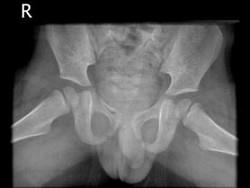

男,请根据其正常盆腔影像图像,判断其最可能的年龄 ( )A、3岁左右B、9岁左右C、12岁左右D、6岁左右E、15岁左右

问题 男,请根据其正常盆腔影像图像,判断其最可能的年龄 ( )

选项 A、3岁左右 B、9岁左右 C、12岁左右 D、6岁左右 E、15岁左右

答案 A